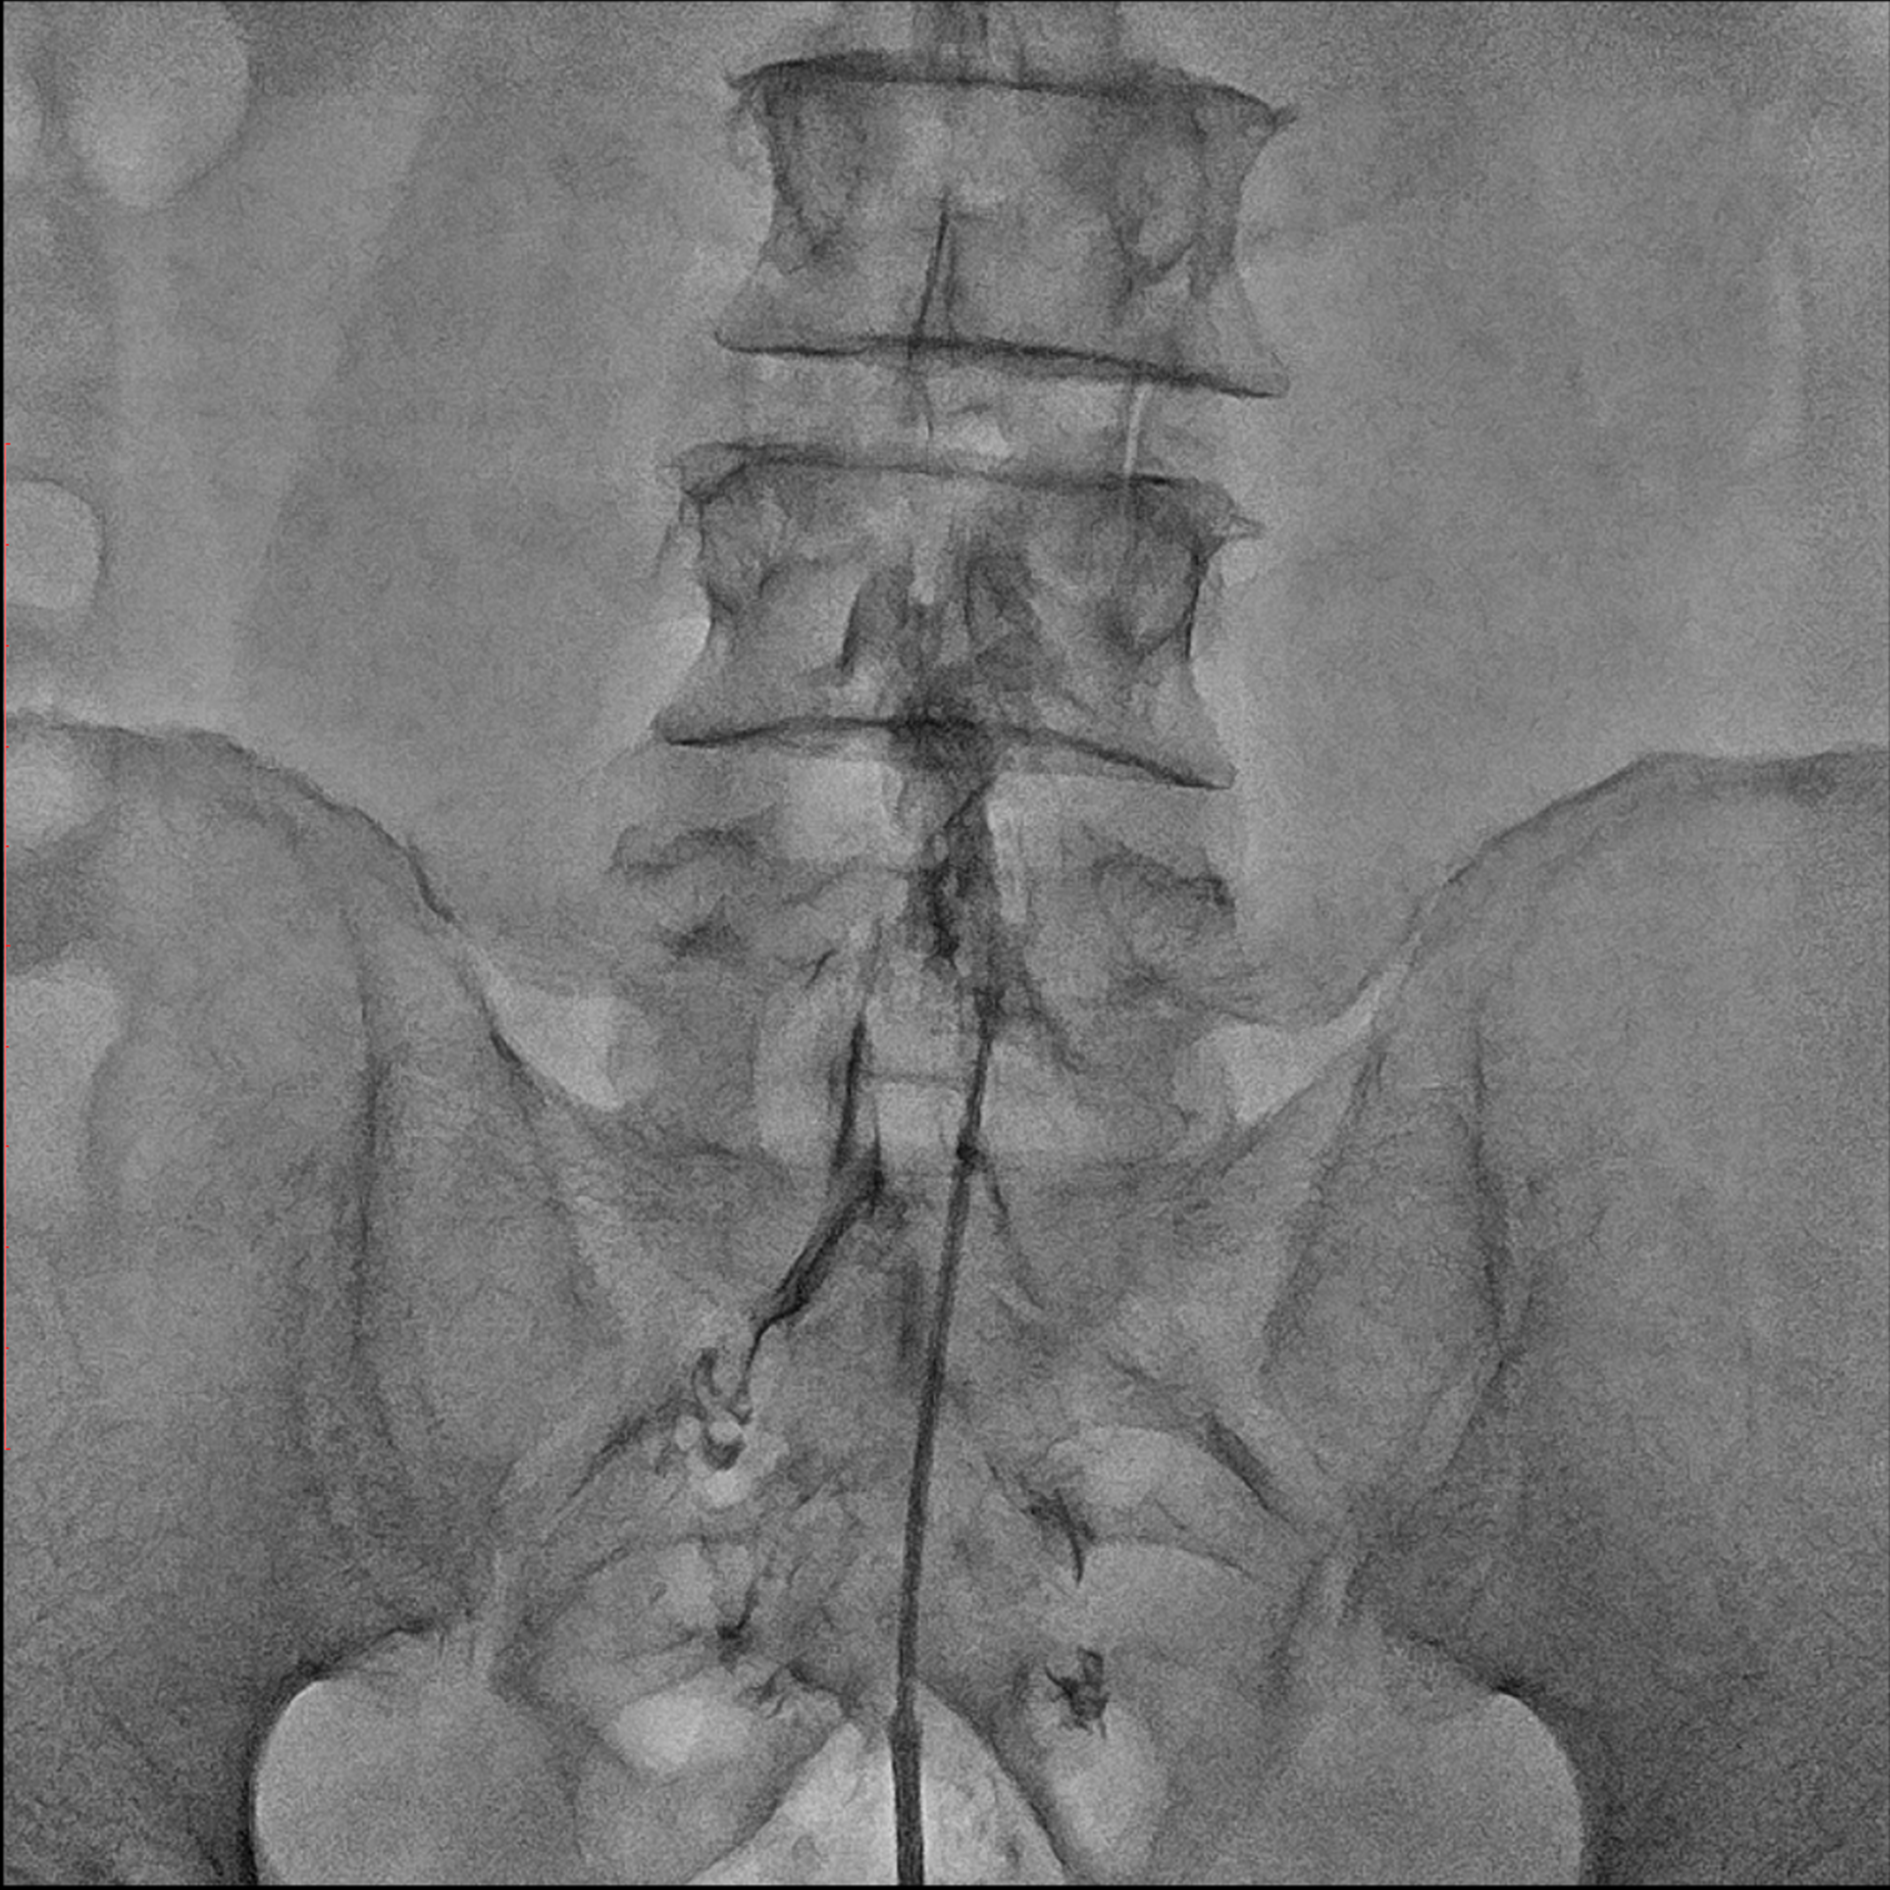

Editorial/Editor's Pick 경막외 유착박리술, Epidural Neuroplasty by Pharmacopuncture Research Lab 2026. 1. 3. 공유하기 게시글 관리 Acupuncture Radiology 관련글 MRI 요양급여의 적용기준 및 방법에 관한 세부사항 MRI 요양급여의 적용기준 및 방법에 관한 세부사항 [신구대조표] Association of AI‑determinedKellgren–Lawrence grade Portable X-ray